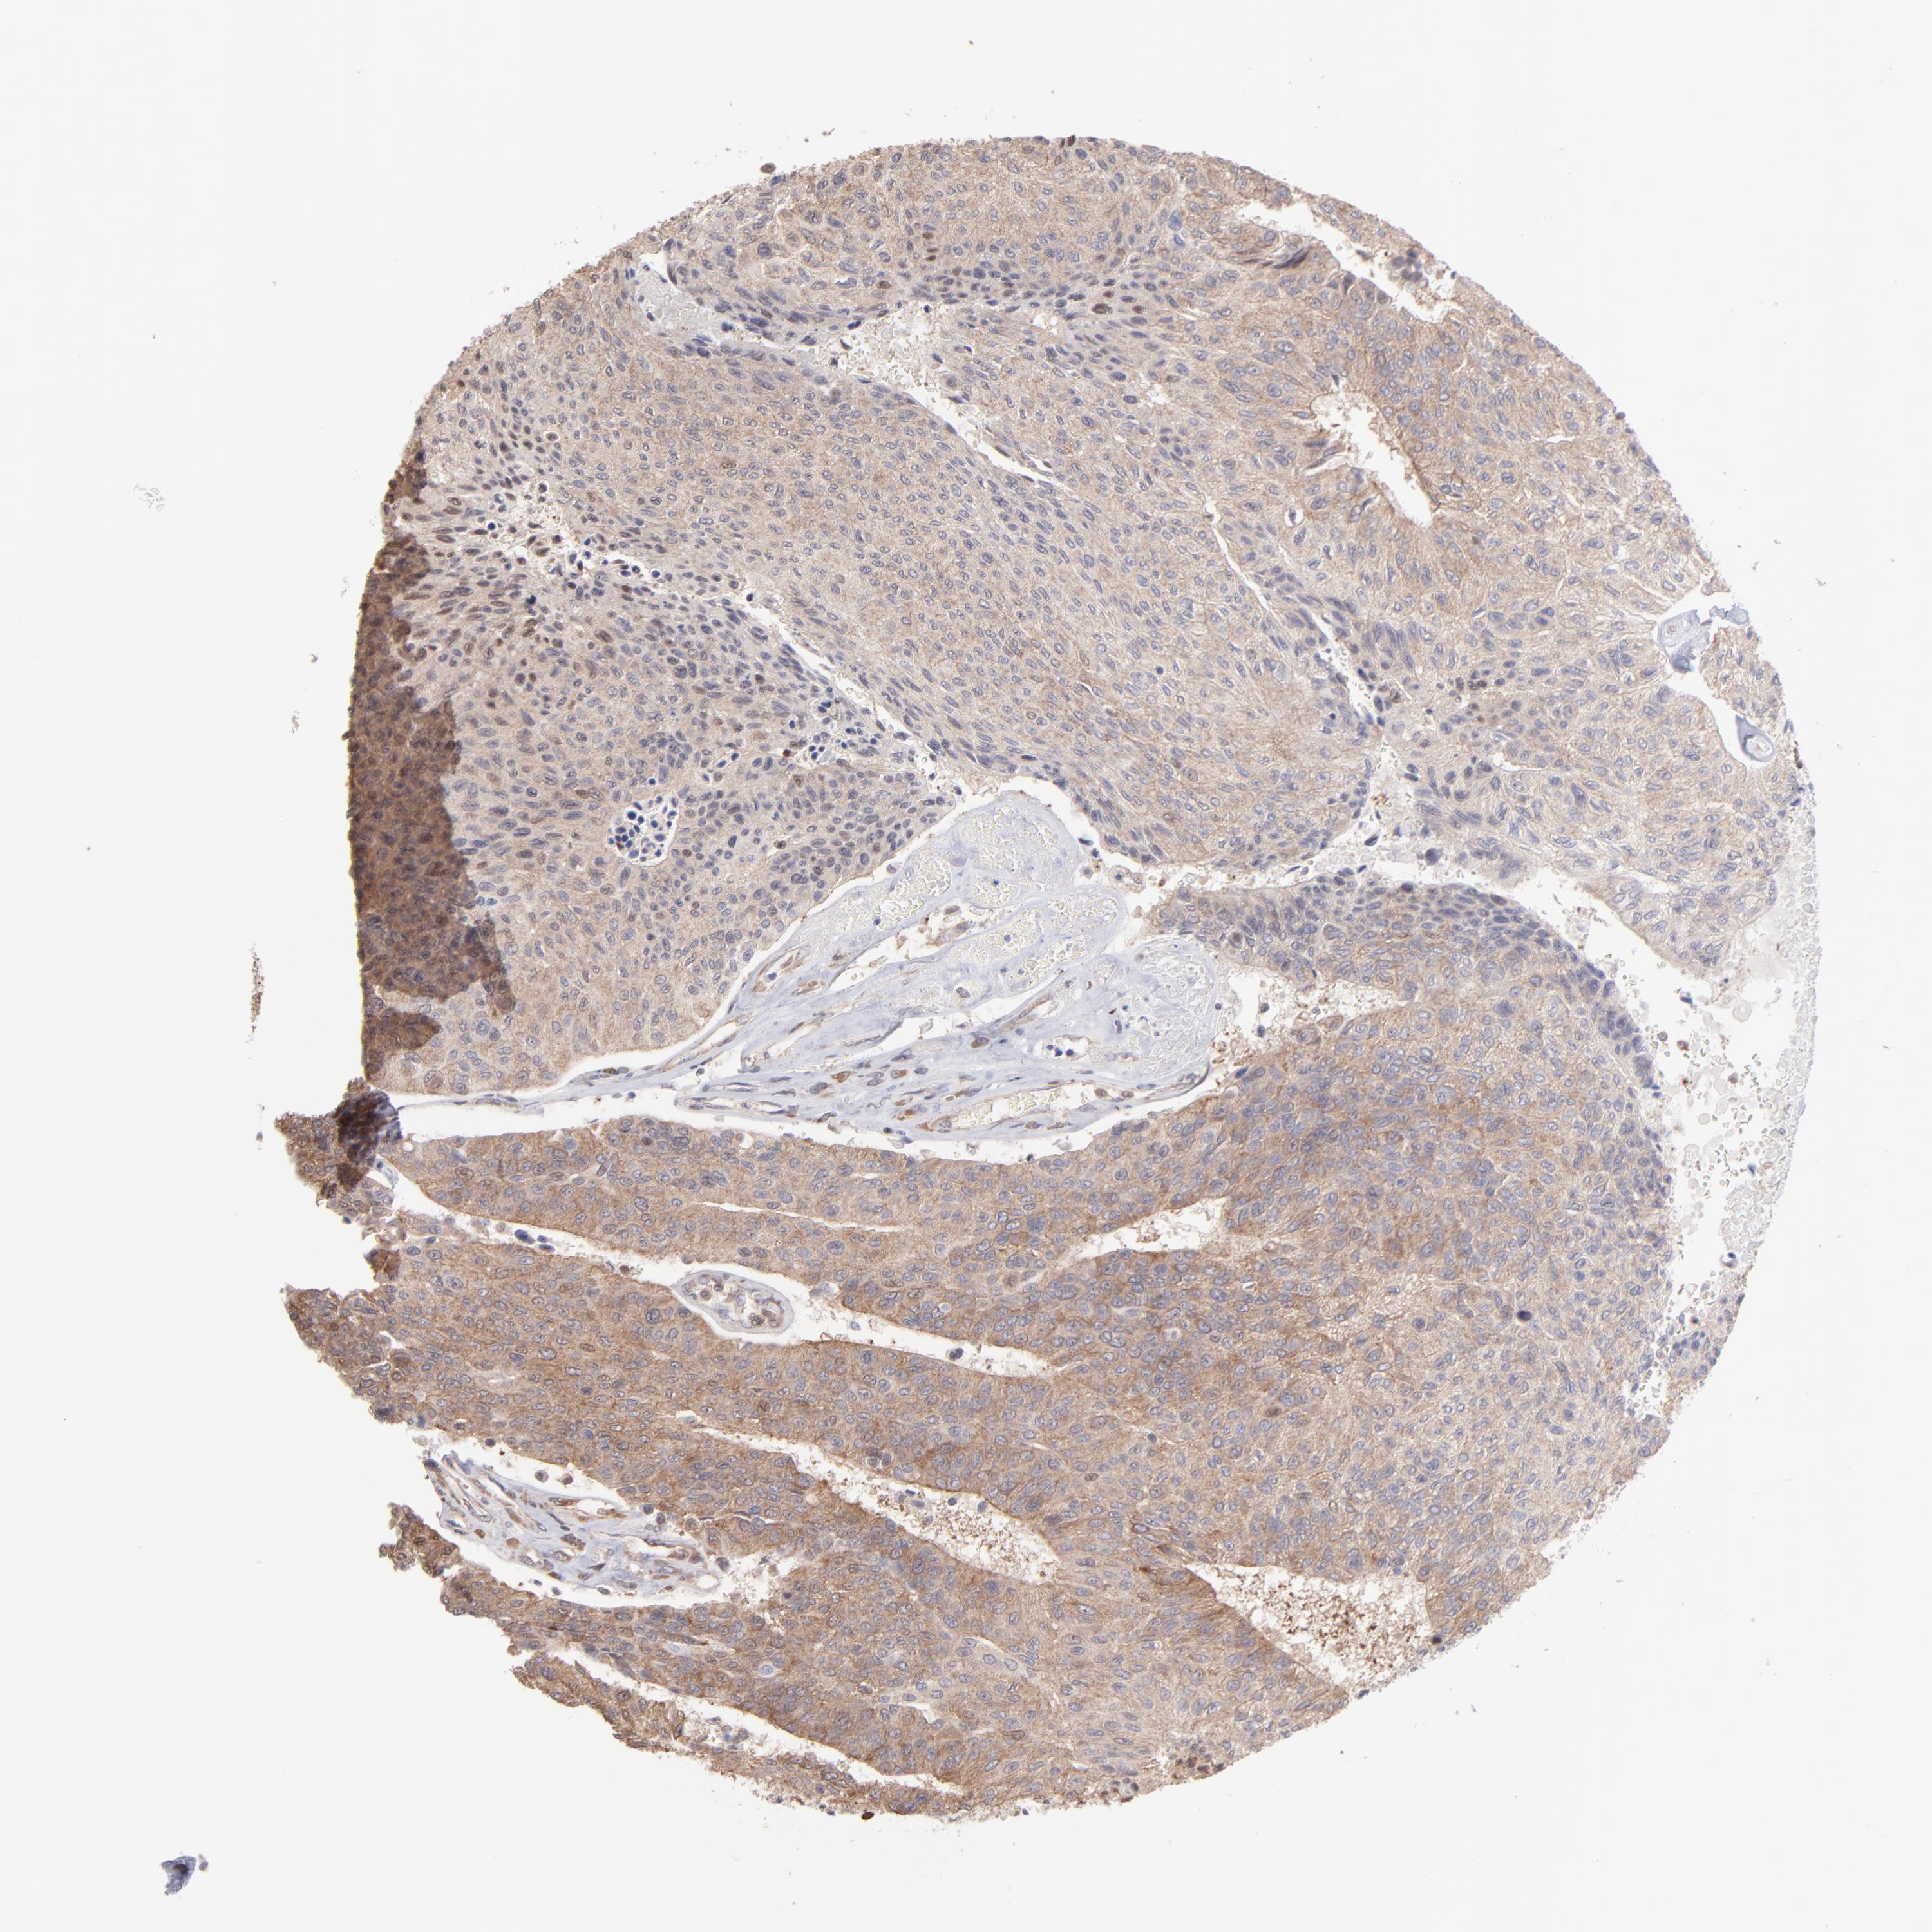

UROTHELIAL CANCER - Protein expressioni

A mouse-over function shows sample information and annotation data. Click on an image to view it in a full screen mode. Samples can be filtered based on level of antibody staining by selecting one or several of the following categories: high, medium, low and not detected. The assay and annotation is described here.

Note that samples used for immunohistochemistry by the Human Protein Atlas do not correspond to samples in the TCGA dataset.

Antibody stainingi

Antibody staining in the annotated cell types in the current human tissue is reported as not detected, low, medium, or high, based on conventional immunohistochemistry profiling in selected tissues. This score is based on the combination of the staining intensity and fraction of stained cells.

Each image is clickable and will lead to virtual microscopy that enables deeper exploration of all samples and also displays staining intensity scores, fraction scores and subcellular localization as well as patient and tissue information for each sample.

Antibody HPA003600

Antibody CAB009337

Urothelial carcinoma, High grade

Urothelial carcinoma, Low grade